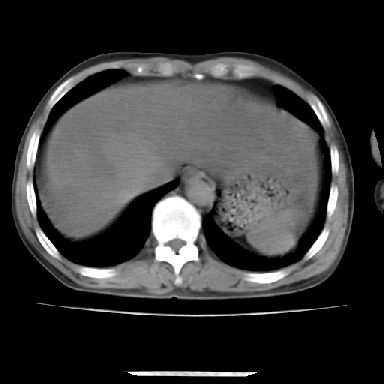

标题: CT7372:脂肪肝?外伤? [打印本页]

标题: CT7372:脂肪肝?外伤?

m 45 车祸,硬膜下血肿

窗宽太宽,调低点就好了,应该是不均质脂肪肝表现,请结合临床,单纯肝挫伤  其内无出血灶很少见,必要时做mri检查

窗宽太大,对比度太差了。局限性脂肪肝也有可能,但是亦不排除外伤性改变,增强扫描应该也还可以鉴别的。

肝内未见出血灶,但不能除外外伤性肝损伤,所示层面应考虑弥漫性脂肪肝.请结合临床必要时做mir检查

肋骨无骨折,腹腔未见游离液体,所以不均匀脂肪肝首先考虑,但如果病人情况允许还是做个增强检查放心

考虑不均匀性脂肪肝,肝包膜下光整,肋骨无异常,无腹水征,不支持肝挫伤。